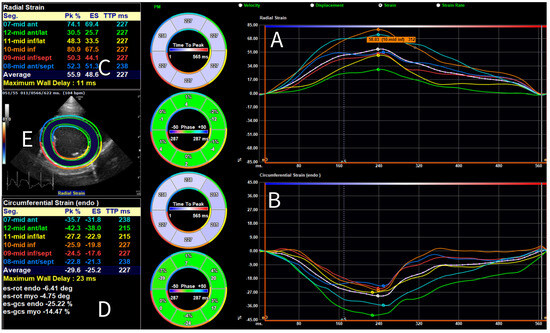

3.2. Results of Strain Analysis